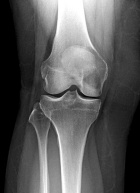

48 yo female w/ 3 mo h/o of R knee pain. Increasing w/o h/o trauma. C/o edema and pain with activity with mild alleviation with rest.

PE: RLE mod effusion about knee with pain at medial femoral condyle. No erythema. Painful ROM 0-130 at knee. No instability. NVI w/o LAN.